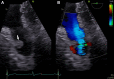

Decision-Making in a Pulmonary Valve Fibroelastoma: The Role of Intraoperative Transesophageal Echocardiography

Keywords: Cardiac fibroelastoma; Cardiac surgery; Cardiac tumor; Pulmonary valve; Transesophageal echocardiography.